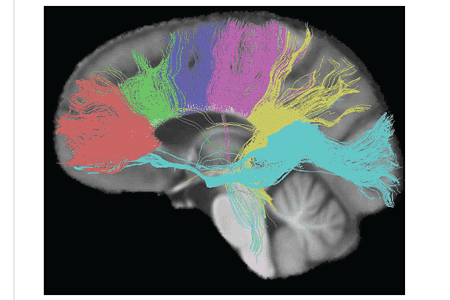

The tractogram pictured shows the nerve tracts from six segments of the corpus callosum, providing linking of the cortical regions between the cerebral hemispheres. Those of the genu are shown in coral; of the premotor, green; of the sensory-motor, purple; of the parietal, pink; of the temporal, yellow; and of the splenium, blue.[11]

Thinner axons in the genu connect the prefrontal cortex between the two halves of the brain; these fibers arise from a fork-like bundle of fibers from the tapetum, the forceps minor. Thicker axons in the trunk of the corpus callosum interconnect areas of the motor cortex, with proportionately more of the corpus callosum dedicated to supplementary motor regions including Broca's area. The splenium communicates somatosensory information between the two halves of the parietal lobe and the visual cortex at the occipital lobe. These are the fibers of the forceps major.[12][13]